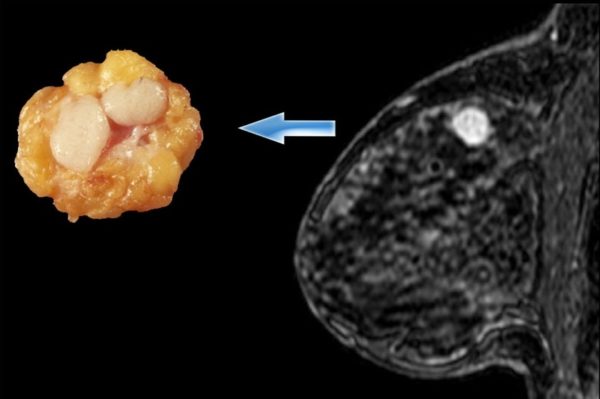

При периканаликулярной фиброаденоме опухолевое образование имеет однородное строение, плотную консистенцию и четкое ограничение от близлежащих тканей.

В некоторых случаях патология сопровождается разнообразными дистрофическими изменениями и образованием кальцинатов.

Обызвествленная фиброаденома

Кальцинаты – это отложения солей, которые накапливаются в различных органах человека.

Что касается наличия кальцинатов в грудной железе, определить их можно только с помощью рентгена или маммографии.